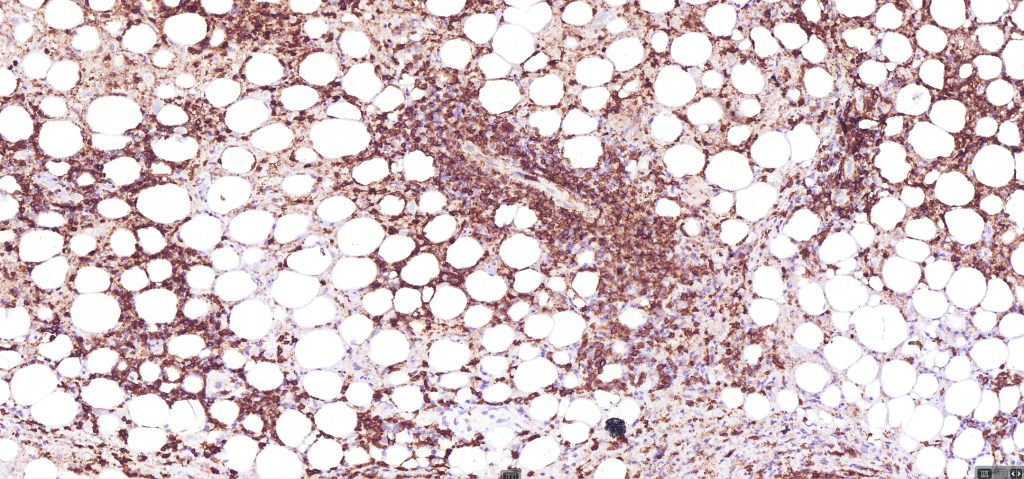

•CD4, CLA, MUM1 +ve

•Granzyme-B, TIA-1 & perforin +ve)